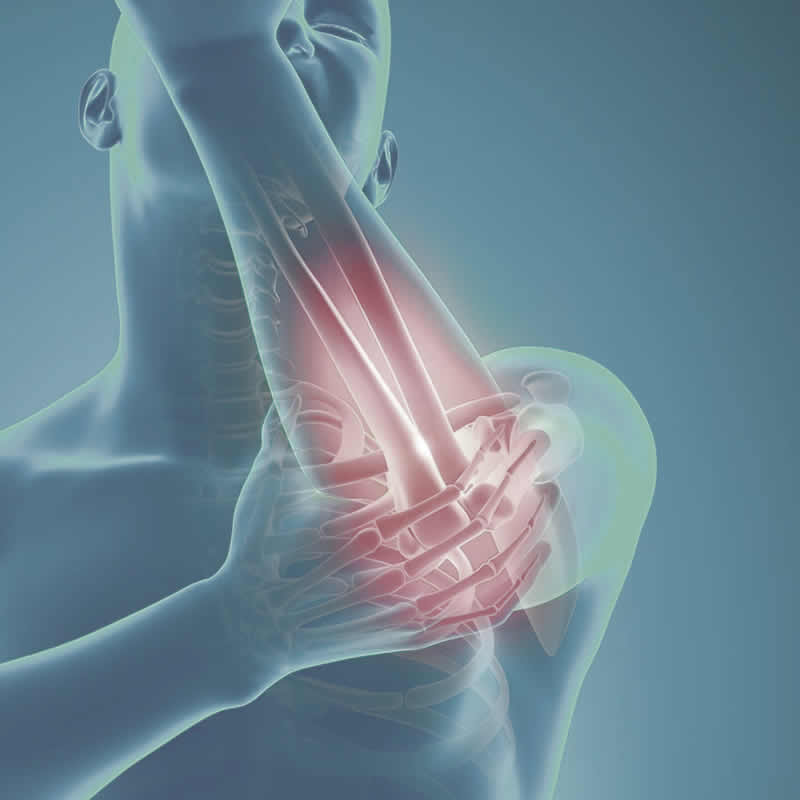

主治項目